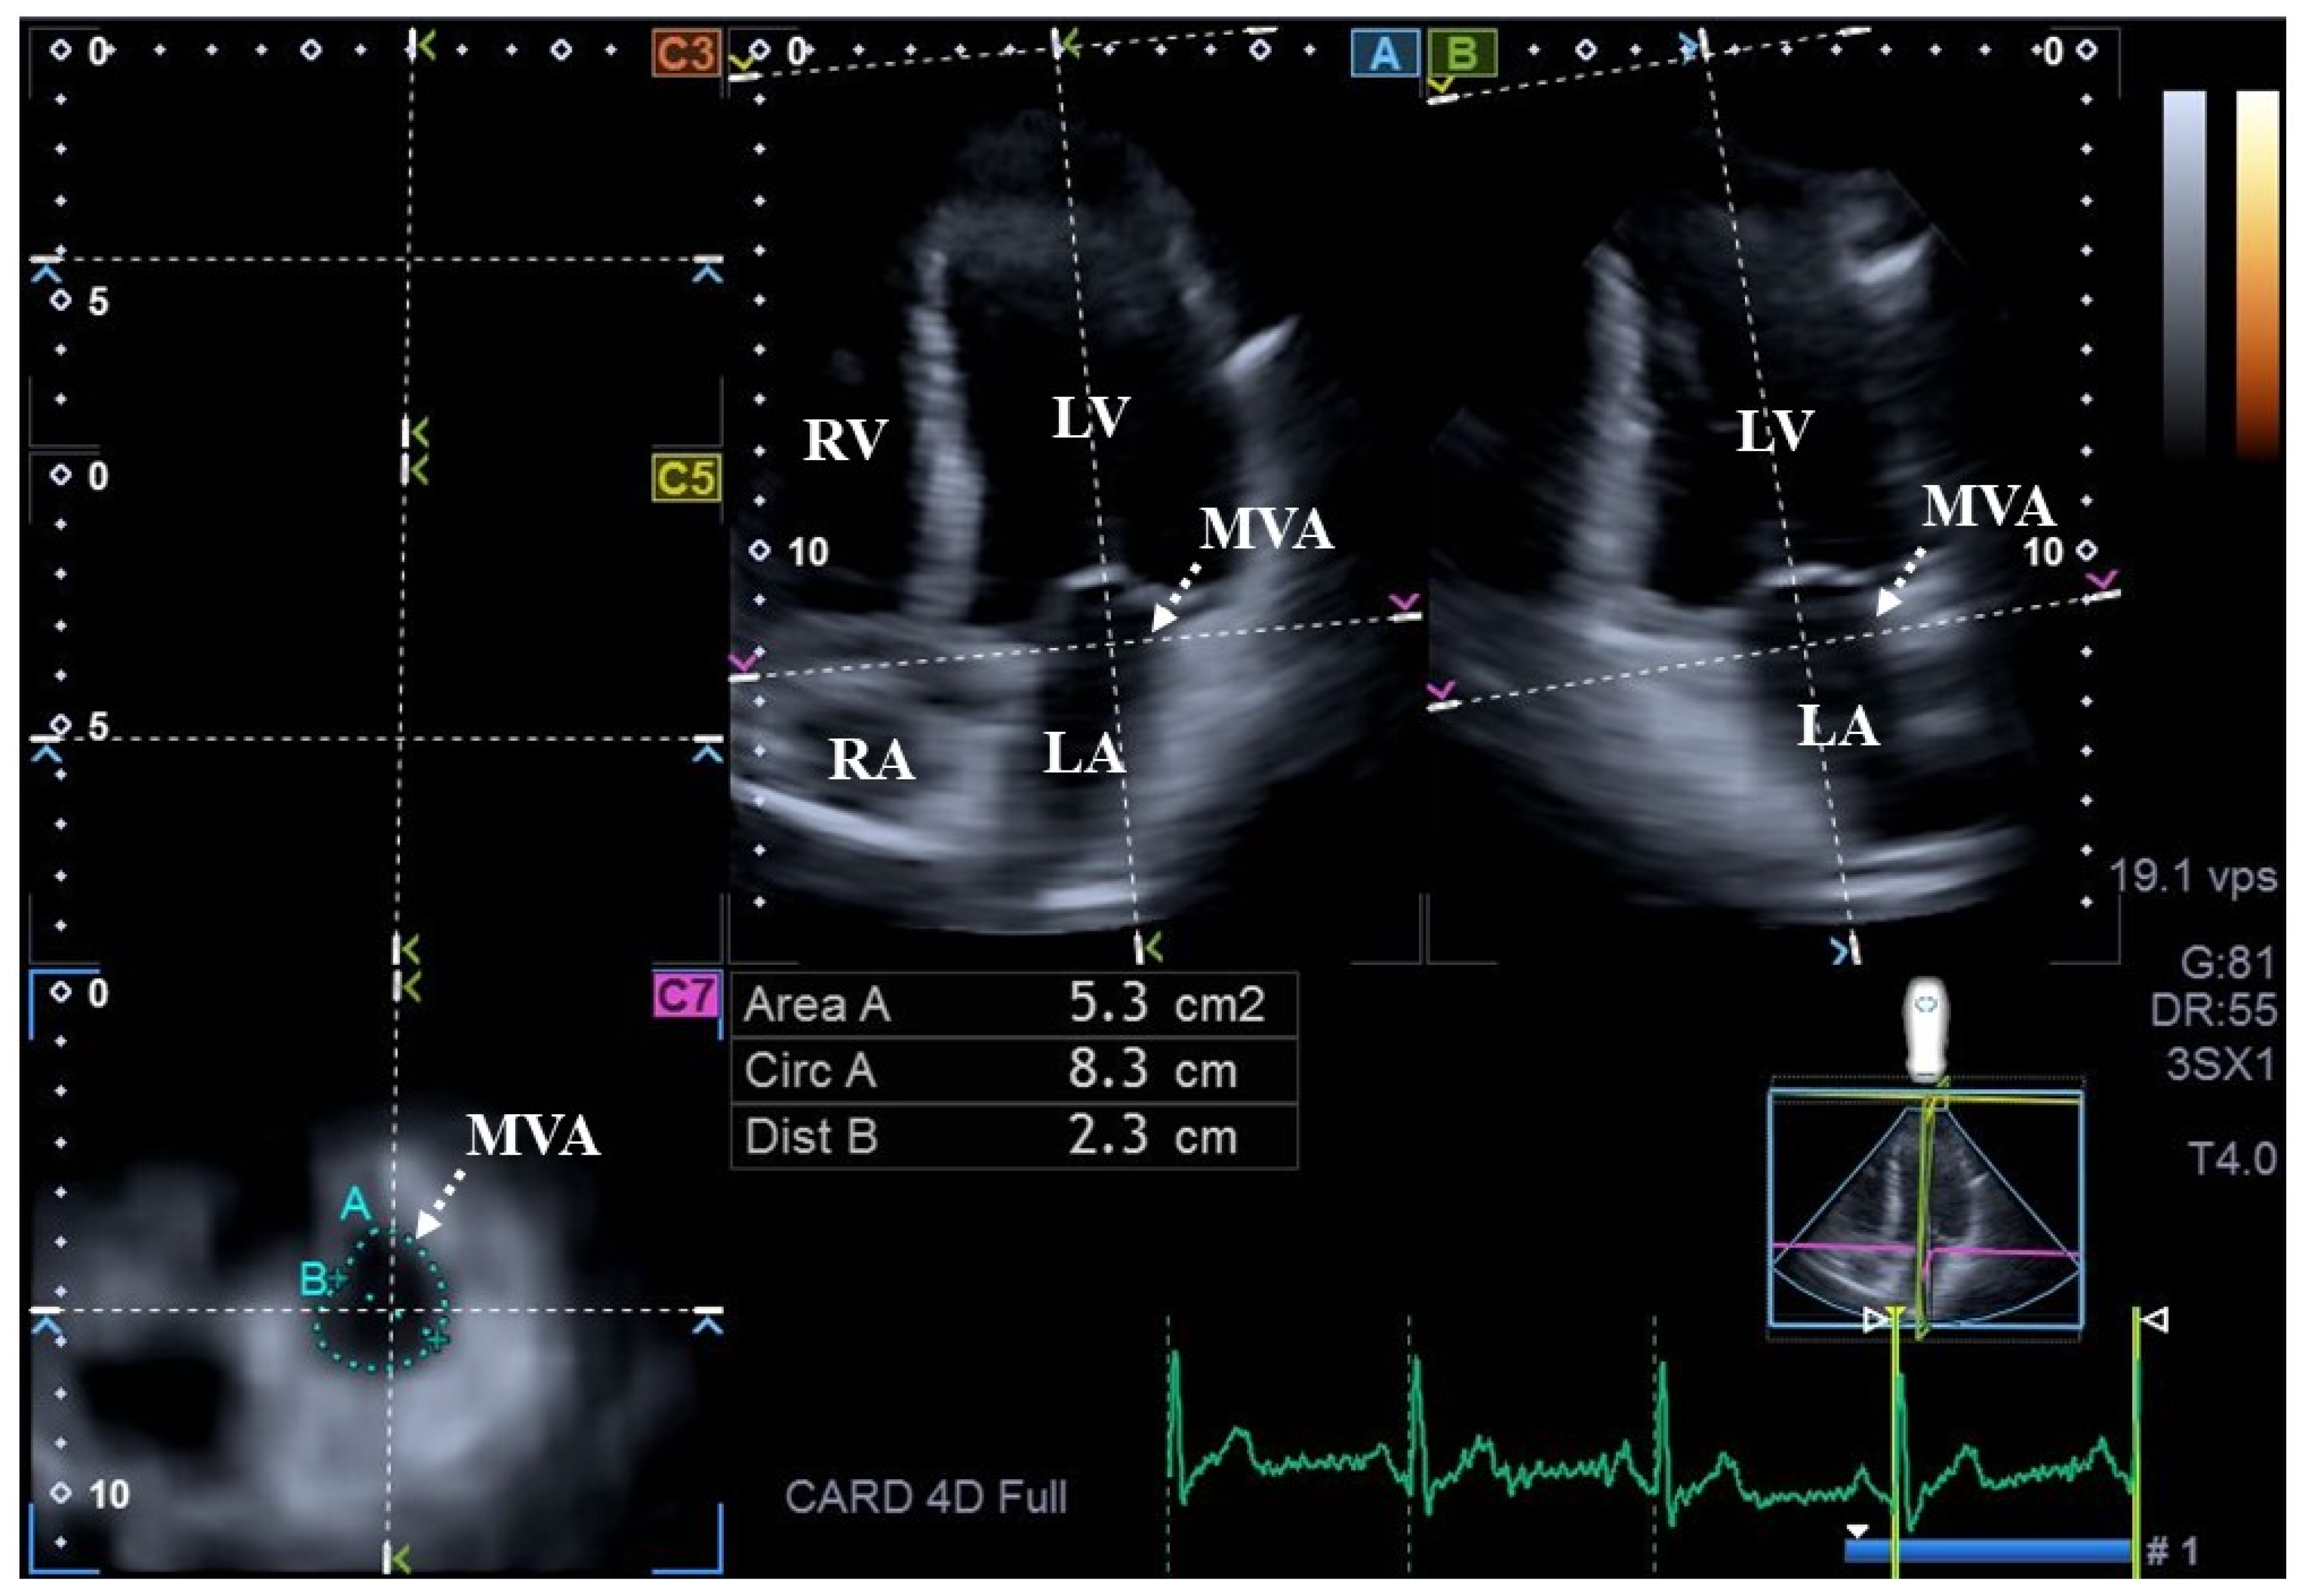

2. Subjects and Methods